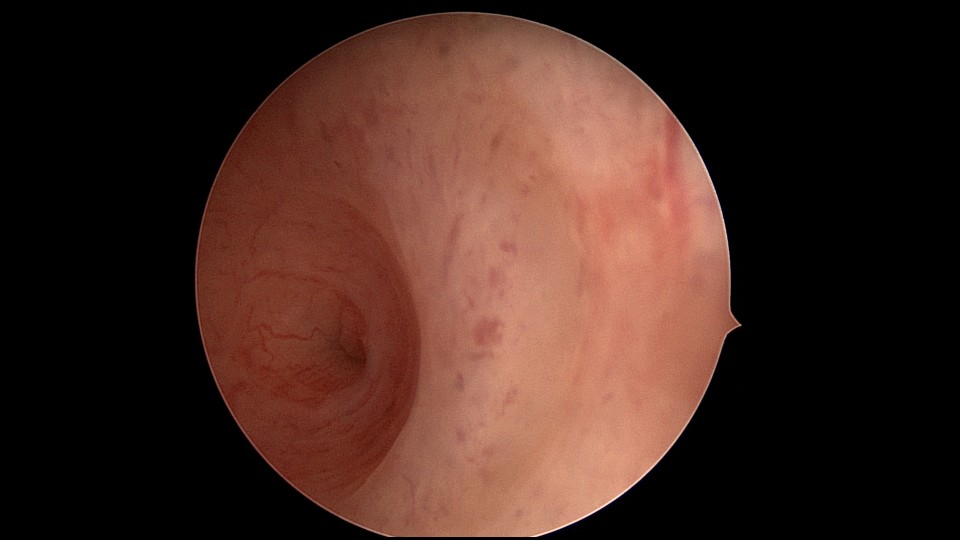

患者29岁,G1P0,继发不孕,2020年8月宫腹腔镜探查,大网膜与腹前壁多处粘连,子宫后壁与直肠前壁广泛粘连,宫腔中央型宽大柱状粘连,宫腔两侧少许粘连。电钩分离盆腔粘连,冷刀分离宫腔粘连,恢复宫腔形态,显露双侧输卵管开口,术中美兰通夜,双侧输卵管通畅。2020年10月宫腔镜二探取球囊,宫腔形态正常,双侧输卵管开口可见。2021年3月自然妊娠,外院足月分娩。现34岁,G2P1。